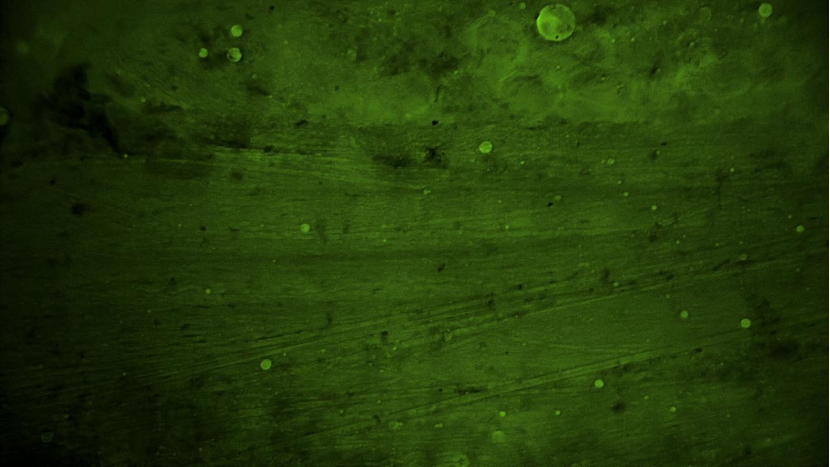

術(shù)中EndoSCell?細(xì)胞圖像如下:

血管組織:可見(jiàn)清晰血管及少量脂肪細(xì)胞,未見(jiàn)腫瘤細(xì)胞